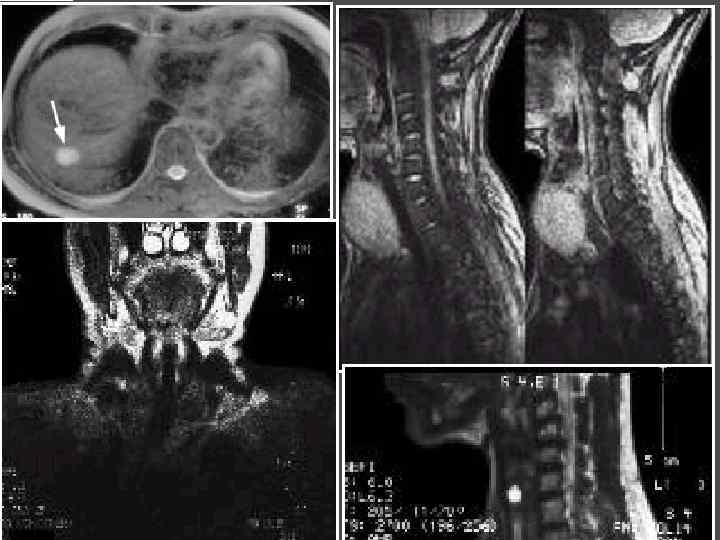

МЕТОДЫ ИССЛЕДОВАНИЯ МОРФОЛОГИИ ЩИТОВИДНОЙ ЖЕЛЕЗЫ Пальпация 2. УЗИ 1. 3. ПТАБ – пункционная тонкоигольная аспирационная биопсия 4. Рентгенография Сцинтиграфия с I 131 6. Компьютерная томография 7. Магнитнорезонансная томография 5.

МЕТОДЫ ИССЛЕДОВАНИЯ ► Определения уровня кальция крови, паратгормона ► Сцинтиграфия паращитовидных желез с Тс99 ► УЗИ ► ПТАБ ► КТ, МРТ ► Денситометрия